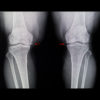

One of the largest MRI-based studies comparing knee injuries between men and women reveals surprising differences in injury patterns based on gender and age. The findings can be used to improve risk assessment and develop early intervention strategies. The study included 13,549 consecutive routine knee MRI exams performed between 2019 and 2024 at...